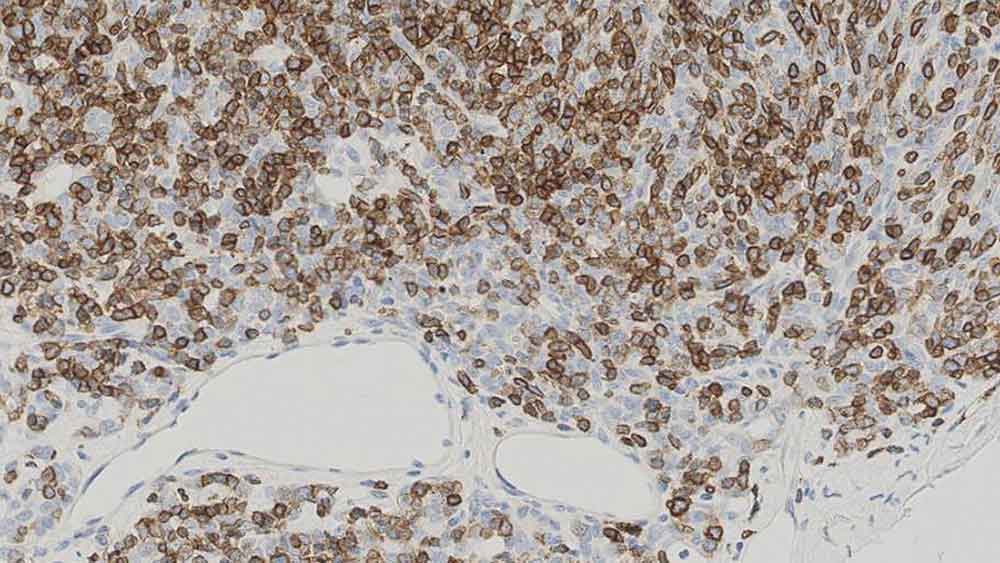

Human bone marrow: immunohistochemical staining for CD71. Note membrane staining of erythroid progenitor cells. CD71: clone 10F11

The CD71 molecule is a type II membrane glycoprotein with a molecular weight of approximately 180 kD. It is known as the transferrin receptor and is composed of two disulfide-bonded 90 kD subunits. The CD71 molecule plays a critical role in cell proliferation by controlling the supply of iron, an essential component for many metabolic pathways, through the binding and endocytosis of transferrin, the major iron-carrying protein. CD71 protein is reported to be expressed on activated B and T cells, macrophages, proliferating cells and metabolically active cells, for example, neurons.